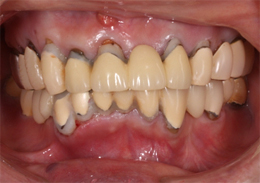

ALL-ON-4(オールオンフォー)の症例写真

上顎のALL-ON-4(ノーベルクリニシャンを使用したフラップレス術式)

- 治療内容

- 上顎に残存していた歯を抜歯。歯肉の治癒後にフラップレス手術にてインプラント埋入を行い、その場で準備してあった上顎上部構造を仮歯として、ねじ固定式で装着

- 治療費用

- 上顎ALL-ON-4:4,000,000円(税別)

- 治療期間

- 6ヶ月